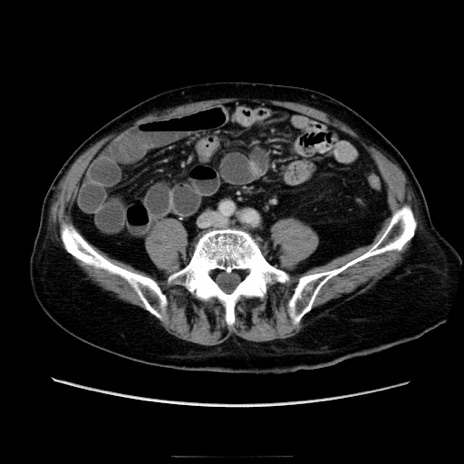

冠状断像